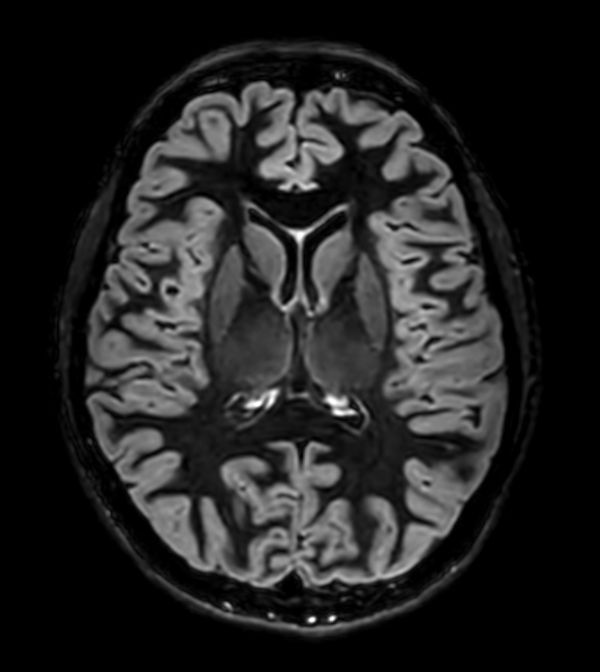

Sagittal 3D T2w TSE

-

3D T2w TSE (Axial reformat)

3D T2w TSE (Coronal reformat)